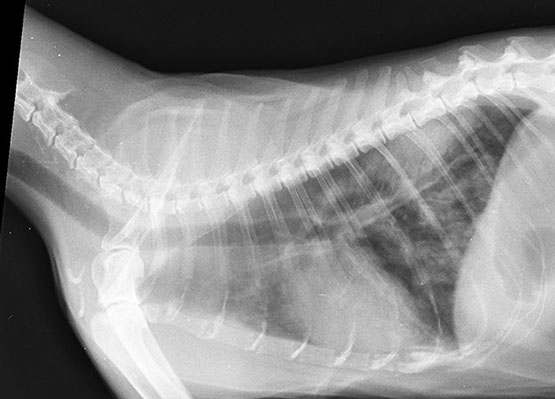

RADIOLOGÍA Y

ULTRASONIDO

Contamos con equipo radiológico digital veterinario para obtener una mucho mejor calidad de imagen y poder así realizar un diagnóstico más acertado en nuestros pacientes, este servicio está disponible las 24hrs y no es necesario realizar cita.

Todas las interpretaciones las realizan médicos veterinarios expertos en el área.